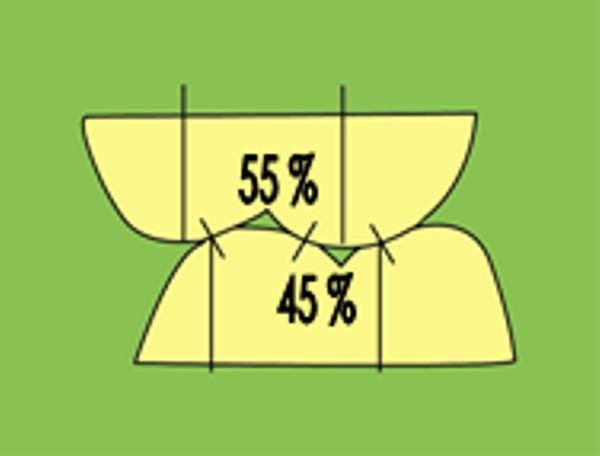

RESUMEN Más allá en el tiempo, respecto de las razones más frecuentes de fracasos como temperatura de fresado, infecciones, falta de fijación inicial, falta de higiene, etc., la OCLUSIÓN recibe sobre sí, la responsabilidad de la permanencia de la osteointegración, como así de la ortofunción del sistema todo. Sometimes ago,conserning the most frecuent reason of failures such as the strawberry action temperature, infections and lack of hygiene…etc.,the OCLUSION has itself the responsability af having the osteointegration well as the allsistem ortofunction . DESARROLLO La valoración de los fracasos en IMPLANTOLOGÍA es difícil de contabilizar sobre todo después del año, ya que el confort logrado por lo general, hace que el paciente realice correctamente sus primeros controles, y después; apoyado en su bienestar; intente subconscientemente olvidar ese período de su vida, que si bien le devolvió su capacidad masticatoria, fonética, social, etc., le ocasionara gastos, molestias, sufrimientos. … la APLICACIÓN de dichas fuerzas, requiere de una exactitud mucho mayor. Los esquemas propuestos a través de los años, no son muchos ni muy variados… I-Evitar las fuerzas tangenciales. II-Repartir las fuerzas lo máximo posible. Sin embargo, muchas veces se confunden los conceptos anteriores con criterios inexactos. Por ej: a-Reducción de las caras vestibulares y palatinas, aceptando que la menor superficie de intercontactos reduce la carga. b-Utilización de la Función de Grupo Posterior, en la creencia de que repartiendo el esfuerzo en las piezas posteriores, ganamos resistencia; a la potencia ejercida por los músculos. c-No permitiendo el contacto excéntrico de un canino implantado, para aliviarlo de las cargas laterales, sobre cargando de esta manera la tabla premolar-molar en el Lado de Trabajo. Algunos conceptos aislados, que forman parte de toda una filosofía de la Oclusión (OCLUSIÓN ORGÁNICA), sean tal vez de ayuda para echar luz sobre los preceptos anteriores. 1º-PROPORCIONES FUNCIONALES DE UN PAR OCLUSAL En la figura siguiente, observamos la relación final masticatoria de un PAR OCLUSAL: En el se ven los contactos puntiformes, producto del choque de superficies redondeadas contra superficies redondeadas («Solo pueden encontrarse en un punto» Ref: Principios Mecánicos Esferoidales.W.Mc.Horris.) Si Miramos con atención este tipo de contactos interoclusales, veremos que la superficie actuante es mucho menor que la superficie total de la cara oclusal: 45% (Fig.1) Por lo tanto, si no es por razones del Pilar de Emergencia para no crear un espacio biológico inadecuado… ¿POR QUÉ REDUCIR LA CARA OCLUSAL VESTÍBULO LINGUALMENTE? (Figs. 2-3-4-5) Si observamos con atención las figuras 2-3-4-5, veremos desde todos los planos , que el área contactante es muy reducida respecto del ancho oclusal total, siendo las fuerzas resultantes , AXIALES al eje implantario. 2º-FUNCIÓN DE GRUPO POSTERIOR. FUNCIÓN CANINA. Tres son las razones por las cuales nos inclinamos a la utilización de la Función Canina. En cambio, en el esquema de FUNCIÓN CANINA, podemos observar que el BRAZO DE POTENCIA, es prácticamente igual al de RESISTENCIA, equilibrando de esta manera la palanca y destruyendo mucho menos las estructuras de soporte(Interface I-H) (Fig. 7) Otra de las razones de peso en este tema es la DIFERENCIA DE ANGULACIÓN que existe entre la cara palatina del canino y las vertientes contactantes del sector premolar-molar. A MAYOR ANGULACIÓN, MENORES FUERZAS LATERALES(Perpendiculares al Plano), y por lo tanto , menor destrucción de la interface Hueso-Implante(Figs. 9-11). DIFERENCIAS EXCITATORIAS DE LOS GRUPOS MUSCULARES. Por último debemos considerar que el intercontacto dentario del sector anterior, estimula excitatoriamente a las fibras anteriores y verticales del temporal (Figs.12-13-14-15), mientras que los contactos posteriores lo hacen con la cincha pterigo-maseterina(Fig. 16-17-18-19) Por lo tanto ,si se comprende el fisiologismo de estos conceptos, es sencillo entender que la sobrecarga de los sectores posteriores es nocivo generando fuerzas tangenciales de Alto Potencial Patológico. 3º-FUNCIÓN DE GRUPO ANTERIOR Las ventajas de un Brazo de Resistencia mayor se acentúan cuando tenemos el esquema de FUNCIÓN DE GRUPO ANTERIOR. Además, debemos tener en cuenta que, durante la función de un Ciclo Masticatorio, es más importante la Desoclusión Final que la Desoclusión Inicial, ya que al ser más larga esta última, es durante el transcurso de su deslizamiento cuando se ejercen fuerzas laterales mayores(Fig. 21) A medida que la punta del canino inferior se acerca a la O.R.C., o sea al Punto de Contacto Intercanino, las fuerzas laterales disminuyen en virtud del acortamiento del brazo de potencia de la palanca, hasta que, al terminar su recorrido, la fuerza es proyectada axialmente sobre el eje del canino superior, debido a que, al margen de la intensidad que la fuerza trae durante el cierre, la dirección de la misma «apunta» en esa dirección. Por eso decimos que los caninos Axializan el Ciclo Masticatorio. Si estamos imitando en lo posible a la naturaleza, no olvidemos este detalle que los dientes naturales provéen, para evitar las fuerzas laterales del canino a la hora de realizar la supraestructura coronaria del mismo. Es ahora menester acentuar que la problemática concreta se manifiesta, no durante la función, sino durante la PARAFUNCIÓN… Cuando estudiamos recorridos de la Dinámica Mandibular, desde el conocido Bicuspoide de Posselt hasta cualquiera de los registros pantográficos, estamos invirtiendo la dirección del movimiento… A.- El primer premolar es el más anterior de la tabla oclusal posterior. Por lo tanto el brazo de resistencia es el mayor de dicha tabla. B.- El lateral, como parte del grupo anterior, cuenta con un empotramiento tipo «clavo largo», y el interseptum lateral -canino, que se opone a la fuerza, es mucho más grueso que la tabla vestibular del primer premolar(Fig.23) C.- Condiciones, las dos anteriores que se favorecen considerablemente, si al enfundar el lateral se logra junto al central una Función de Grupo Anterior. D.- De manera más artificiosa, la instalación de una placa de relajación, soluciona durante la noche lo nocivo de las fuerzas laterales. Veamos un par de casos, como ejemplo de lo dicho: Paciente de 54 años que se presenta a la consulta portando prótesis completa superior y antagonista natural que soporta fundas de porcelana. Obsérvese la función de grupo posterior ejercida, y las consecuencias de la misma: Otro paciente que presenta fractura de la cúspide fundamental de un onlay de porcelana antagonista de cinco piezas implantadas (Fig.27). Radiográficamente se observa la desinserción de uno de sus abuttments cementados (Fig.28). En el Lado de Trabajo (LT), no existe el canino encargado de desocluir la zona afectada (Figs.29-30) Como corolario, cabe entonces una pregunta: ¿Es el Implante en el canino quien debe preservar de patología oclusal al resto del sistema…. ¿Es el Implante…un medio…o un fín? BIBLIOGRAFÍA 1- Dibujos tomados del libro del mismo autor: «OCLUSIÓN ORGÁNICA… UN CAMINO HACIA LA REHABILITACIÓN ORAL»(en preparación) 2- «NEUROFISIOLOGÍA DE LA OCLUSIÓN» 3- «OCLUSIÓN Y FUNCIÓN» 4- «FUNDAMENTOS, TÉCNICAS Y CLÍNICA EN REHABILITACIÓN BUCAL» 5- «OCLUSIÓN Y REHABILITACIÓN» 6- «DISFUNCIÓN TEMPOROMANDIBULAR» 7- «PROCEDIMIENTOS CLÍNICOS Y DE LABORATORIO DE OCLUSIÓN ORGÁNICA» 8- «ESTUDIO ELECTRÓNICO DEL MOVIMIENTO MANDIBULAR» 9- «OCLUSIÓN: CONCEPTO PARA EL CLÍNICO» 10- «IMPLANTOLOGÍA CONTEMPORÁNEA» 11- «OCLUSIÓN Y DIAGNÓSTICO EN REHABILITACIÓN ORAL» 12- «PRINCIPIOS DE OCLUSIÓN»